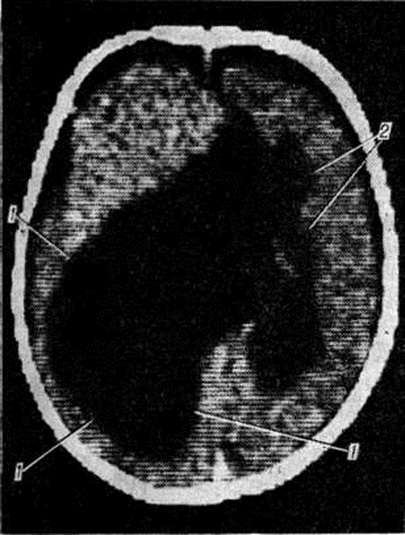

Рис. 2.

Макропрепарат головного мозга при ложной поликистозной порэнцефалии (горизонтальный разрез): стрелками указаны множественные внутримозговые кистозные полости, располагающиеся в белом веществе головного мозга.

Ложной порэнцефалией называют полости, располагающиеся в ткани мозга, но не доходящие до поверхности головного мозга и не сообщающиеся с желудочками мозга (рисунок 2).

Эти полости могут располагаться в одном или обоих полушариях головного мозга, главным образом в его белом веществе, бывают одиночными и множественными, сообщающимися между собой. Внешний вид извилин коры головного мозга, как правило, не изменён. В стенках ложных кист выявляется рубцовая ткань.